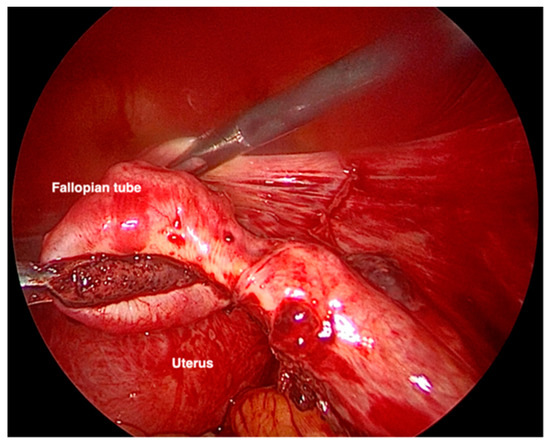

Due to the clinical course, the gestational age, and the size of the ectopic pregnancy, it was decided to take a surgical approach. The laparoscopic evaluation showed 700 mL of hemoperitoneum and an intact but swollen and bleeding right tuba, on the verge of breaking at the level of the ampulla (Figure 2). Right salpingectomy was performed, and the specimen removed was sent for histological examination. The exam confirmed the diagnosis of ectopic pregnancy with embryonic residues and chorionic villi compatible with the first trimester of pregnancy.

Figure 2. VLS image of the salpinx enlarged and bleeding due to ectopic pregnancy.